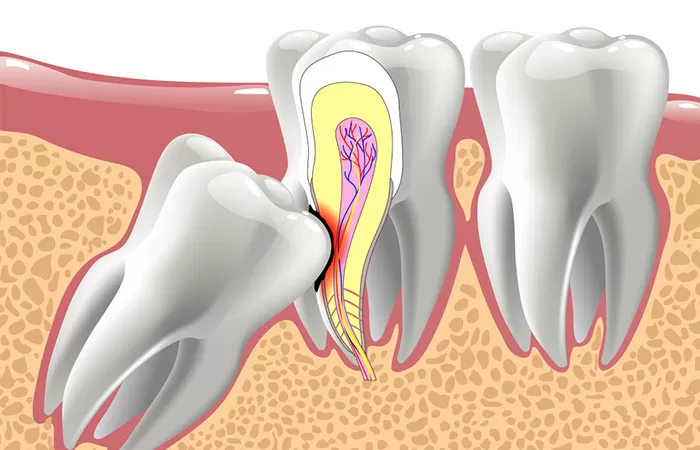

Ngược lại, khi không có đủ chỗ mọc, răng khôn sẽ mọc lệch hay răng mọc ngầm hoặc mọc kẹt gây đau đớn, gây khó chịu và ảnh hưởng xấu đến những răng lân cận. Vì mọc ở vị trí rất khó làm sạch lại hay gây nhồi nhét thức ăn, răng khôn sẽ là nơi trú ngụ và sinh sôi của các loại vi khuẩn gây viêm nướu, hôi miệng, không những răng khôn mà răng cối thứ 2 kế cận cũng sẽ bị sâu. Khi đó, việc nhổ bỏ răng khôn mọc lệch là điều cần thiết.

Tình trạng răng: 2 răng khôn hàm dưới mọc ngầm và lệch gần, làm tổn thương răng kế cận. Răng nanh hàm trên bên phải mọc ngầm và lệch chỗ. Các răng mọc ngầm cần được tiểu phẫu để ngăn ngừa biến chứng và ngăn ngừa gây sâu răng kế cận.